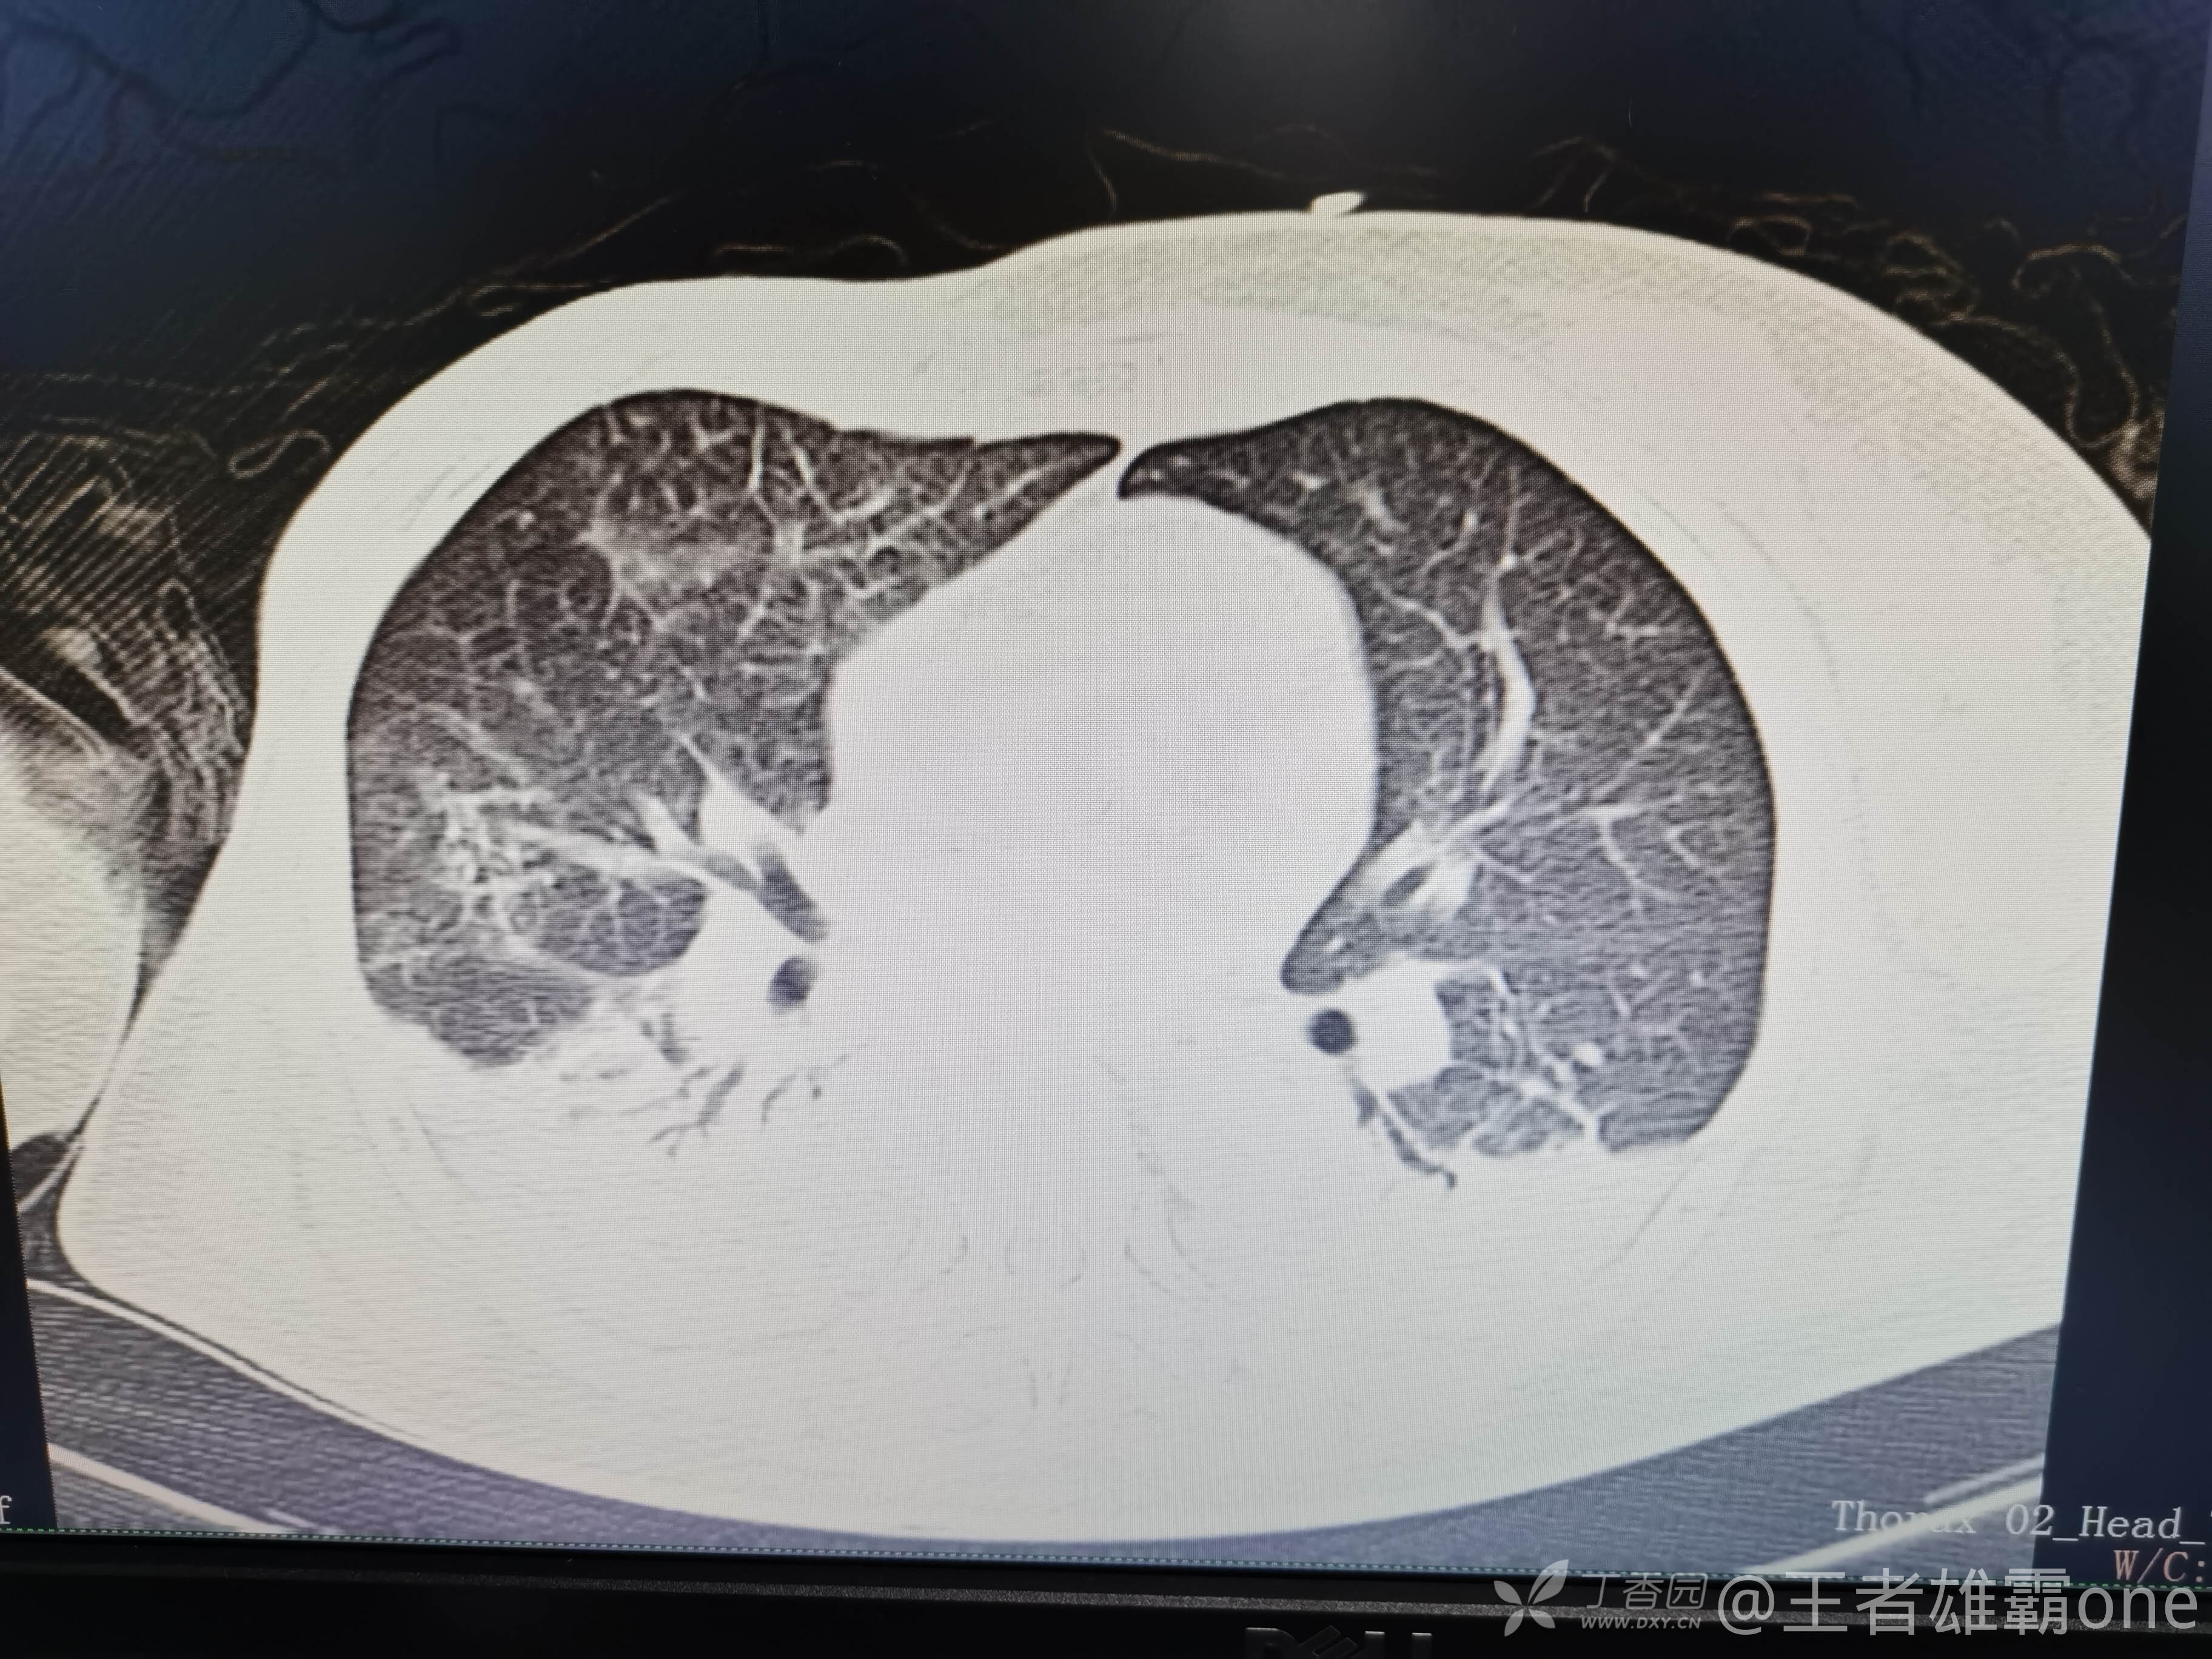

西门开心 推荐63岁女性,因车祸致短暂神志不清、多处疼痛4h入院。简单病史:伤后送至医院急诊就诊。完善头胸腹CT等检查,完善新冠核酸、血常规等化验。血常规提示血红蛋白62g/L。头颅CT提示未见明显外伤性改变。胸腹部CT视频见下:

5.肺挫伤

6.双侧多发肋骨骨折

12.双侧胸腔少量积液

早上复查血常规:血红蛋白100g/L,白细胞11.1×109/L,血小板29×109/L。凝血功能:APTT37.9s,纤维蛋白原3.01g/L,凝血酶时间18.6s,D二聚体21530ug/L。生化:白蛋白36.2g/L,胆红素指标正常,谷丙56U/L,总胆红素38mmol/L,直接胆红素12.1mmol/L,谷草57U/L,肌酐91.1ummol/L,尿素13.97mmol/L,超敏C反应蛋白142.1mg/L。降钙素原17.70ng/ml。脑钠肽前体2164pg/ml。复查胸部CT: